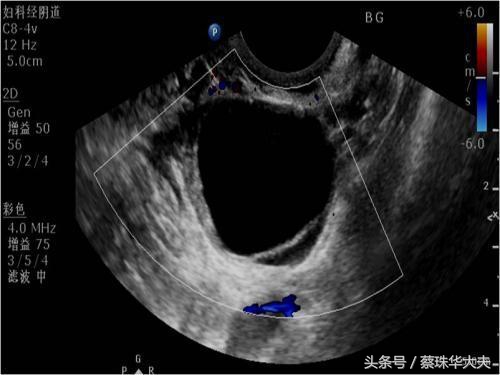

卵泡囊肿的特点是囊液澄清,囊壁非常光滑。所以很多女性体检是发现卵巢囊肿,一般都建议月经周期第五天或月经干净了马上复查。

黄体囊肿特点里面回声有点杂,B超会经常描述成混合性回声。如果当月排出来的卵没有怀孕,那黄体囊肿就没有任务了,就自行萎缩掉。